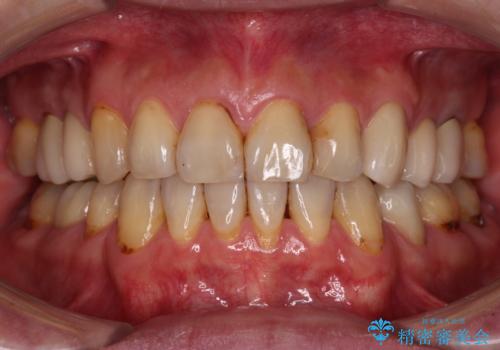

- むし歯による奥歯の痛みを気にして来院された患者様です。

神経にまでむし歯の及んでいる歯や、既に根管治療がされている歯に痛みがあったため、まずは根管治療を行うこととしました。

その後、以前行った抜歯矯正の後戻りをインビザライン・ライトにより改善し、むし歯や銀歯はオールセラミッククラウンにて補綴治療することとしました。

痛みは速やかに引き、銀歯や黒く変色したむし歯がセラミッククラウンで自然な色合いに仕上がり、患者様には大変満足していただきました。